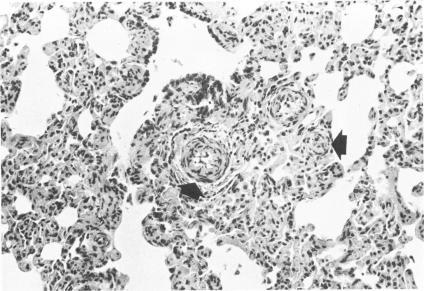

Animal model: pulmonary hypertension, cor pulmonale and endocardial fibroelastosis in monocrotaline-intoxicated nonhuman primates.

Am J Pathol. 1973 Mar;70(3):489-92.

Animal model: pulmonary hypertension, cor pulmonale and endocardial fibroelastosis in monocrotaline-intoxicated nonhuman primates.动物模型:用野百合碱中毒的非人灵长类动物建立肺动脉高压、肺心病和心内膜纤维弹性组织增生症模型